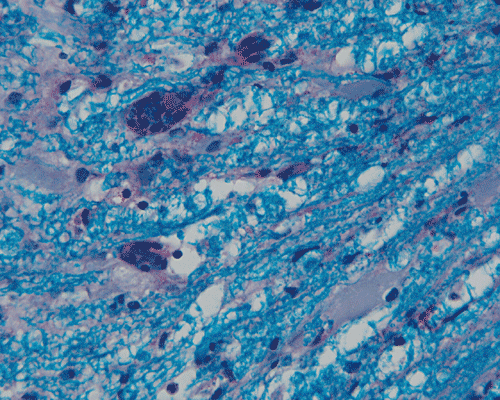

F. Squash |

G. Squash |

Q. LFB-PAS |

Panel A to E are MR images. Panel F and G are taken from intraoperative cytologic preparation. Panel H to M are taken from frozen section. Panel N and O are from paraffin section. These sections are stained by hematoxylin-eosin stain. Panel P is immunohistochemistry for neurofilament proteins. Panel Q is stained by Luxol fast blue-Periodic acid Schiff (LFB-PAS) stain.

Pathology:

| DIAGNOSIS: Eosinophilic myelitis. |

Pathology of eosinophilic myelitis

Eosinophilic myelitis is featured by lymphocytic infiltration accompanied by a varying intensity of eosinophils. Both the myelin and axons may be damaged. Axonal spheroids can be seen and indicate primary axonal damage rather than secondary damage following demyelination 14, 15. Destruction of axons in the lesion may well explain the relatively poor recovery of this condition. There is increase in eosinophils in CSF in the our under discussion. However, the CSF studies are normal in two previous studies 14, 15.

The eosinophils play an important role in causing the damages. Infiltration by eosinophils and depositions of activated products of eosinophils are commonly seen in atopic disorders, such as atopic bronchial asthma, allergic rhinitis and atopic dermatitis. The presence of atopic diathesis as well as eosinophilic cationic protein deposition suggests that atopy may represent one of the risk factors for developing eosinophilic myelitis. Eosinophilic cationic protein is one of the neurotoxic proteins released by activated eosinophils Eosinophil cationic protein and other products of eosinophils such as major basic protein have been shown to be neurotoxic. The infiltrating eosinophils may therefore well contribute to the neural damage.

Since eosinophils are chemo-attracted to Th2 cytokines such as IL-5, the presence of eosinophils suggests a local production of Th2 cytokines in spinal cord lesion of atopic myelitis. Th2 cytokines may also be found in the blood and their role on eosinophilic myelitis is uncertain. As demonstrated in this case, increased level of IgE has also been demonstrated in eosinophilic myelitis.

In addition to eosinophils, predominant CD8 T-lymphocytes infiltration is commonly observed 14. Selective infiltration of CD8 T-lymphocytes into the parenchyma, may suggest the critical pathogenic role of these cells, such as a cytotoxic role rather than a secondary suppressive one. In atopic disorders, acute lesions are characterized by predominant CD4 T-lymphocytes infiltration over CD8 T-lymphocytes infiltration, while CD8 T-lymphocytes predominate in chronic lesions. Therefore, the predominant infiltration of CD8 T-lymphocytes seen in the spinal cord may reflect the chronic nature of the lesions.